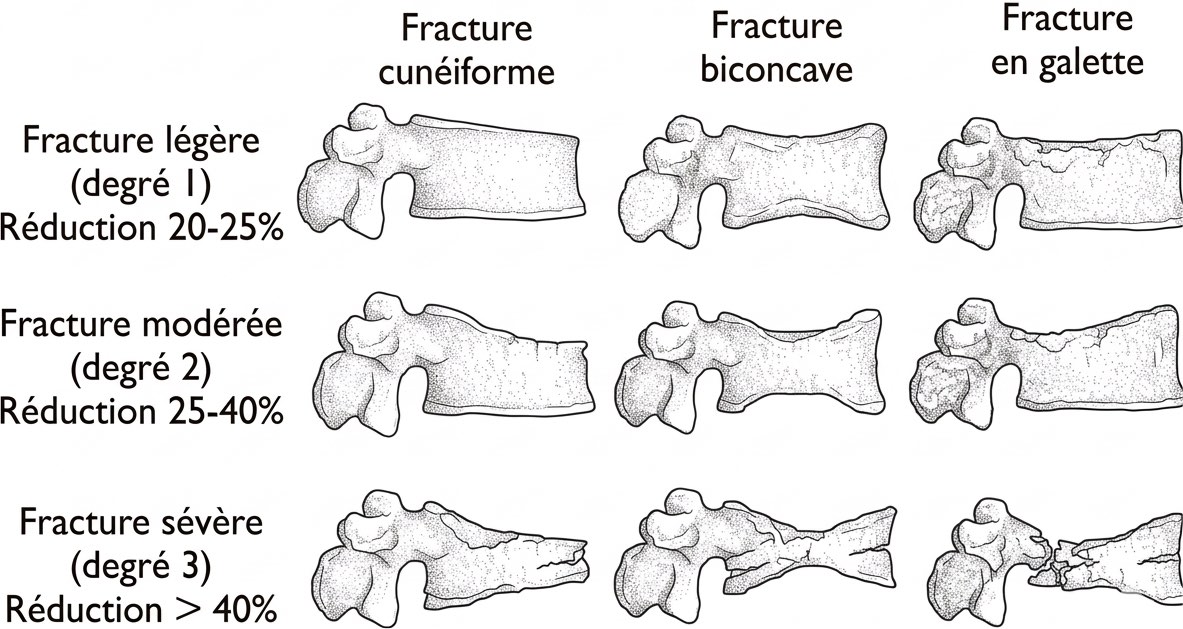

Fractures

ostéoporose vs malin

- symétrique dans le plan frontal, rétropulsion coin postéro-sup, vide intrasomatique

- multiples tassements en-dessous de T6

- persistance de signal graisseux dans la moelle en T1

- si doute => T1 post-gado montre une homogénéisation du signal